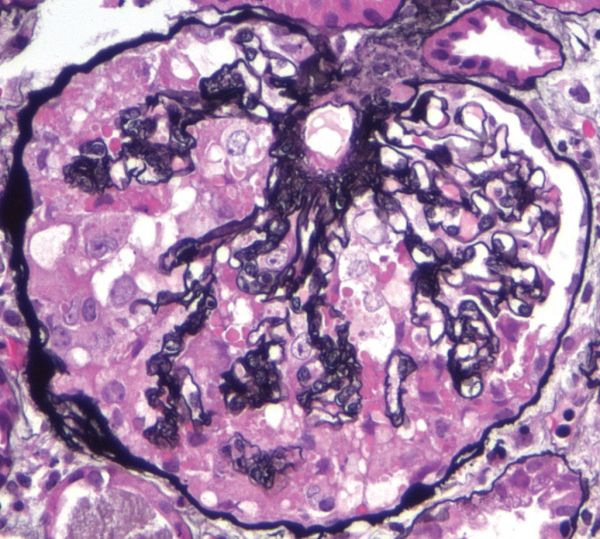

Патологические процессы: анатомия и примеры